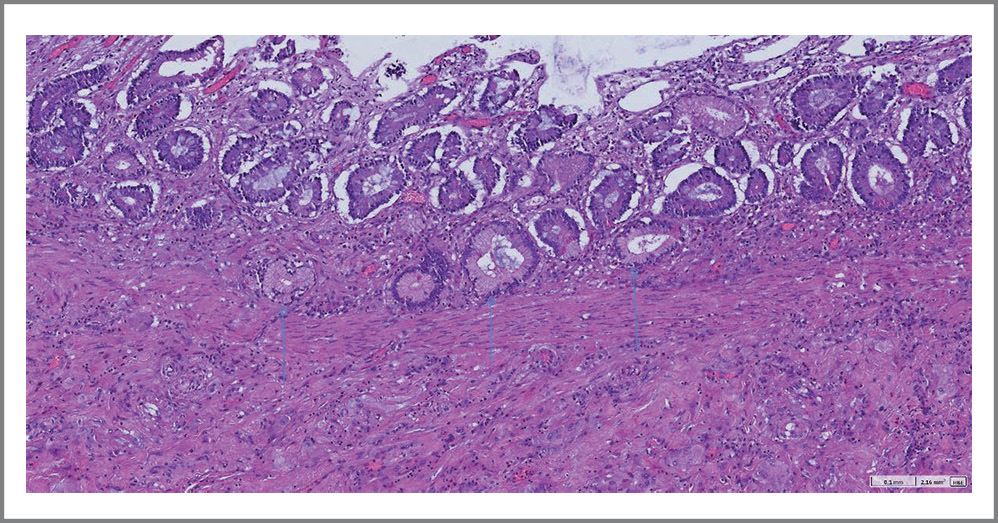

Проведено микроскопическое исследование операционного препарата. Обнаружены фрагменты стенки ТК с язвенным дефектом глубиной до подслизистой основы, занимающим около 50% окружности СО. Дно дефекта представлено фиброзно-склеротической тканью со зрелой грануляционной тканью, наложениями фибрина и гранулоцитов по поверхности. СО в краях дефекта с очагами псевдопилорической метаплазии. Артерии и артериолы в дне дефекта с очагами гиалиноза. Мышечный слой стенки и серозная оболочка типичного морфологического строения. В жировой клетчатке брыжейки обнаружен лимфоузел с реактивными изменениями.

Заключение. Микроскопическая картина характерна для хронической язвы ТК с активным воспалением, началом формирования фиброзной стриктуры (рис. 5–8).

Рис. 5. Микроскопические изменения в стенке резецированной ТК. Псевдопилорическая метаплазия в краях язвенных дефектов ТК на фоне хронического воспаления.

Fig. 5. Microscopic changes in the wall of the resected jejunum. Pseudopyloric metaplasia in the edges of ulcerative defects of the jejunum with chronic inflammation.

Рис. 7. Микроскопические изменения в стенке резецированной ТК. Псевдопилорическая метаплазия в краях язвенных дефектов ТК на фоне хронического воспаления.

Fig. 7. Microscopic changes in the wall of the resected jejunum. Pseudopyloric metaplasia in the edges of ulcerative defects of the jejunum with chronic inflammation.